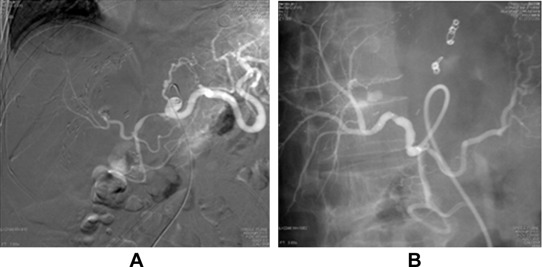

A 52-year-old patient underwent living donor liver transplantation for alcoholic liver cirrhosis with Child–Pugh C status in 2010. This patient had diabetes mellitus, atrial fibrillations, and chronic kidney disease prior to the operation. Postoperative course was uneventful and the patient was discharged 1 month after the transplantation. Two months after the transplantation, the patient had a spike of fever and an elevation of liver function test values. Ultrasonography of the abdomen showed liver abscess. CT-guided pigtail catheter drainage of liver abscess was performed. E. coli and Enterococcus faecium growth was noted on pus culture. After 1 week of antibiotic treatment, pus culture data revealed the growth of E. faecium, Stenotrophomonas maltophilia, and yeast-like micropathogen. The patient was continuously treated with antibiotics and fluconazole. After 2 weeks of catheter drainage, the patient developed upper GI bleeding and melena. Panendoscopy was performed, and the results revealed bleeding from the ampullary papilla. Celiac angiography showed A saccular pseudoaneurysm at the distal proper hepatic artery with anastomotic narrowing of the proximal hepatic artery and poststenotic dilatation. Subacute bleeding was noted from the pseudoaneurysm. After selective cannulation of the right hepatic artery, successful angioplasty of the hepatic artery with placement of endovascular stent graft (Abbott, Jostent, Abbott Vasculat Inc. Santa Clara, CA, USA, 3 mm/26 mm) to cover pseudoaneurysm was performed ( Fig. 2). Postprocedure angiography showed successful exclusion of a pseudoaneurysm with a good flow to the graft and marked improvement in the luminal diameter of the hepatic artery without significant residual stenosis. The patient was continuously treated with antibiotics, recovered well, and was discharged 1 month later.

Hepatic artery angiography for Case 2. (A) Pseudoaneurysm at the anastomotic ...

Figure 2.

Hepatic artery angiography for Case 2. (A) Pseudoaneurysm at the anastomotic site. (B) Pseudoaneurysm disappeared after placement of stent graft.